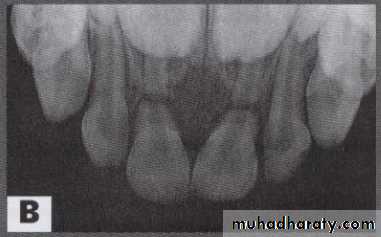

Radiographic evaluation

Indication for radiograph;• To detect root fracture

• Ascertain extent of root development

• To determine resorption

• To detect foreign body in soft tissue

• To detect jaw fracture

• To note position and stage of development of permanent teeth

• To detect size of pulp chamber

• To detect periapical radiolucency

• For follow-up evaluation